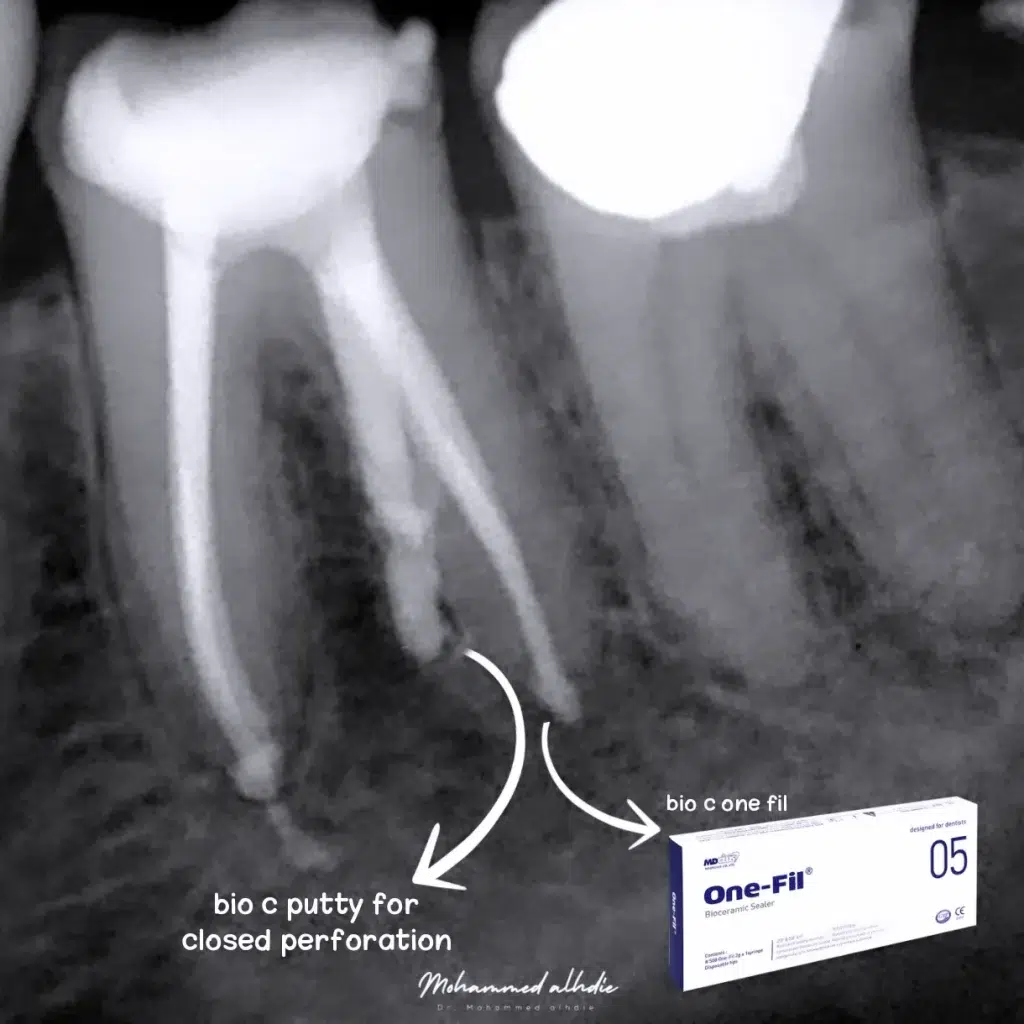

الصورة رقم 8: الحشو النهائي باستخدام مانع التسرب الخزفي الحيوي من onefil وإغلاق الثقب باستخدام مادة bio c butty